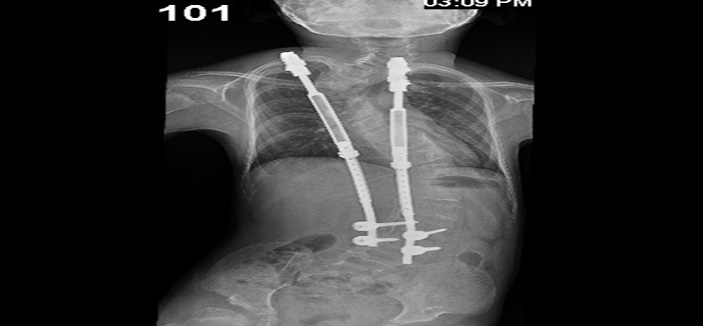

وأوضح د. الحنيطي بأنه تم إخضاع الطفل للفحوصات المخبرية وأشعة الرنين المغناطيسي (M.R.I) والتصوير المقطعي المحوري (C.T. Scan) والأشعة العادية (X-Rays) حيث أوضحت النتائج وجود ميلان حاد بالعمود الفقري بزاوية إنحناء قدرها 80 درجة في إتجاه اليمين بالفقرة القطنية الأولى وانحراف آخر في الفقرة الصدرية الخامسة بزاوية انحراف (65) درجة.

وأشار الدكتور الحنيطي إلى أنه بعد دراسة الوضع الصحي للطفل تبين حاجته الفورية لإجراء عملية إصلاح العمود الفقري التي استغرقت (3) ساعات تم فيها التعديل بإستخدام أحدث جهاز في العالم والمعروف باسم الفيبتور V.E.P.T.R (Vertical Expandable prosthetic Titanium Rib ) الذي يتميز بالمحافظة على نمو العمود الفقري والصدر والرئة بصورة طبيعية. مشيراً إلى أن هذا الجهاز مخصص للأطفال فقط .